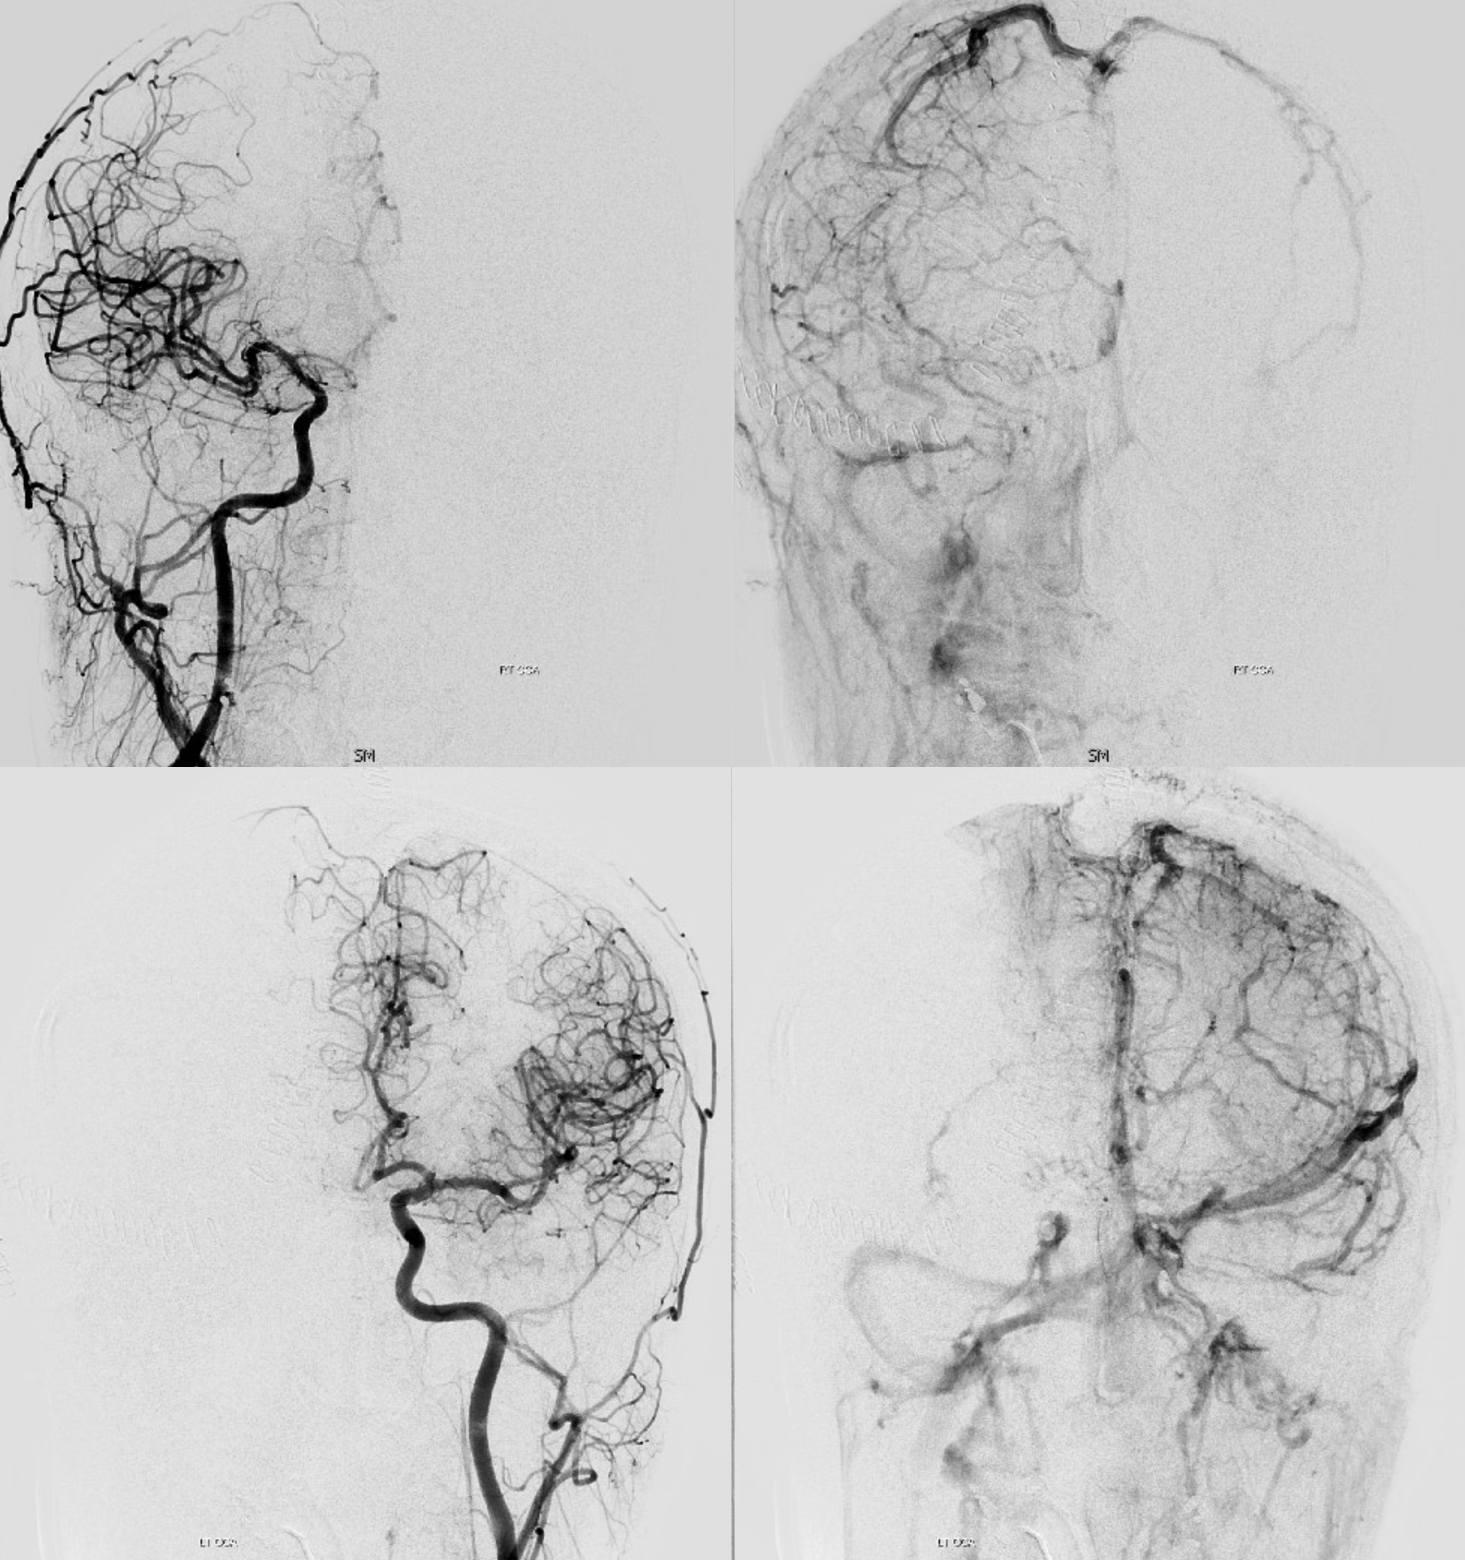

Following embolization, resection, recurrence (as frequently the case with childhood AVMs) and gamma-knife, things look good. Stereo, of course.

Following embolization, resection, recurrence (as frequently the case with childhood AVMs) and gamma-knife, things look good. Stereo, of course.

Below is a case of severe venous sinus thrombosis and secondary parenchymal venous infarcts

The explanation for the above tragic pattern is below. On the right, sigmoid and transverse sinuses are patent. However, the Labbe is hypoplastic, and majority of outflow used to go to the Trolard, into the now occluded SSS. There is no other effective way to go — the trolard tries to decompress via a left diploic vein, and convexity tries to access the deep venous system (which normally should not be well-seen in setting of hypoplastic right A1 segment). The left situation is much better, as well-developed superficial sylvian veins drain into the patent Cavernous Sinus. Thus, despite thrombosis of the left transverse and sigmoid sinuses, the left hemisphere is doing better, while the right one, which has patent transverse and sigmoid sinuses, is devastated.

Post venous thrombectomy — with limited results. Note presence of same left diploic vein as seen in right ICA injection, and connection between the distal superior sagittal sinus and the deep venous system via the inferior sagittal sinus.